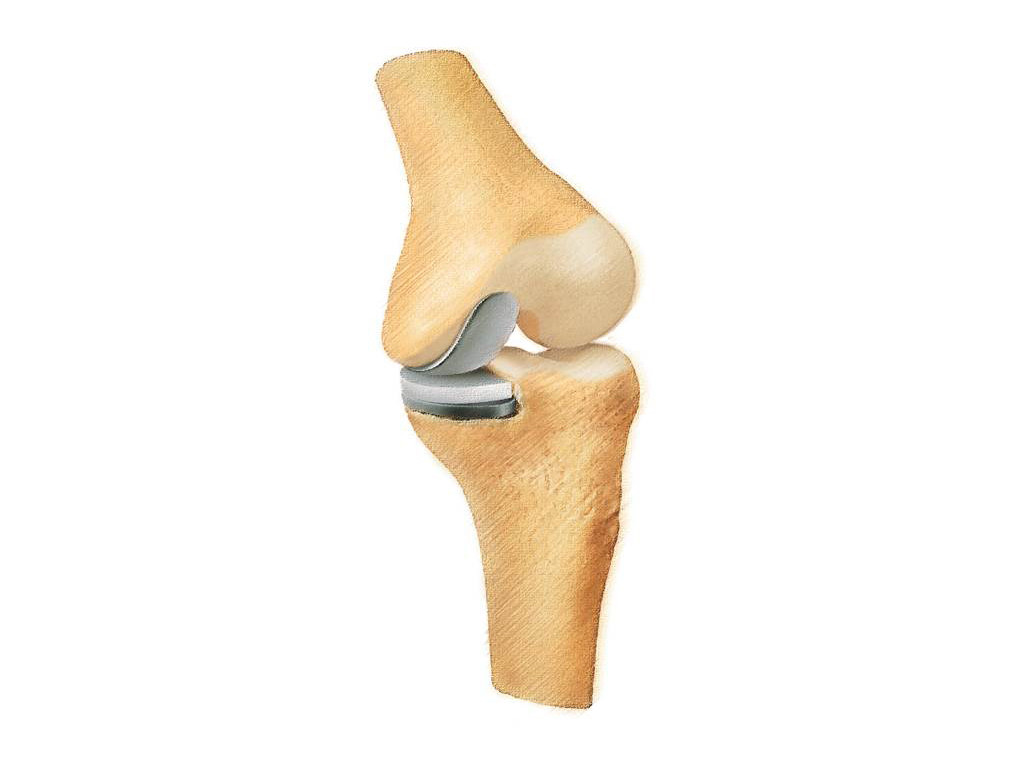

Oberflächenersatz („Knie-TEP“)

Bei einem Verschleiß der gesamten Knorpelfläche bei noch intakten Seitenbändern empfehlen wir einen Oberflächenersatz.

Hierbei werden nur wenigen Millimeter vom Knorpel entfernt um das Implantat passgenau aufzubringen.